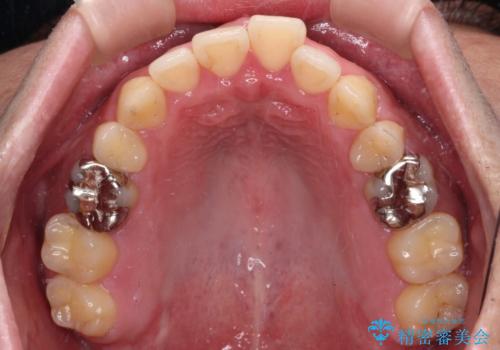

- 矯正装置

- インビザライン

舌の突出癖によるオープンバイトになり、前歯の叢生が後戻りしていました。

インビザラインの特性を活用して奥歯の咬み合わせを圧下させることで、前歯のオープンバイトを改善さえることができました。